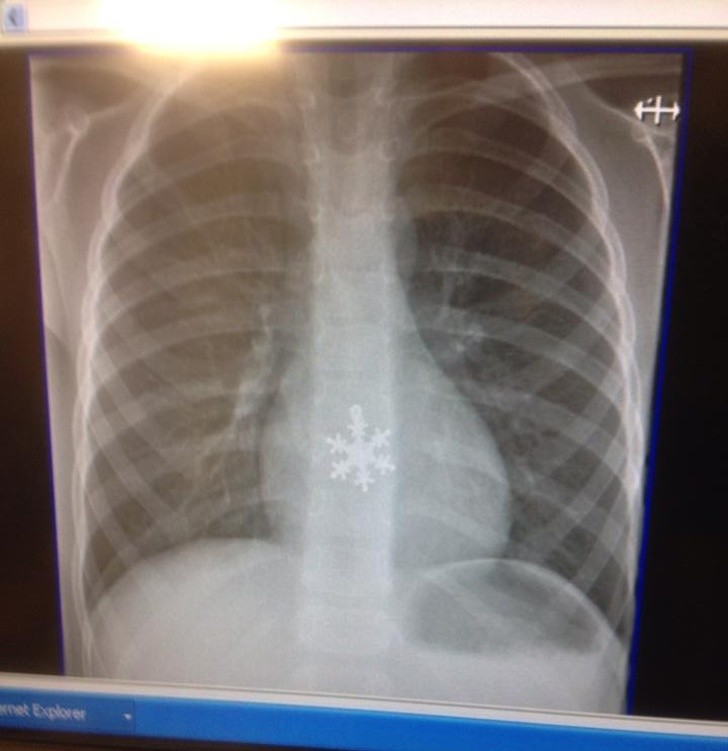

Radiologi so tako že precej navajeni, da na rentgenskih posnetkih vidijo čudne stvari in nekatere izmed teh, ki smo jih za vas zbrali v galeriji, jih sploh niso presenetile. Tukaj je 15+ odštekanih in na trenutke šokantnih rentgenskih posnetkov.